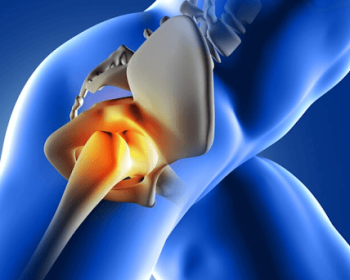

Primary hip replacement is a surgical procedure to replace a damaged hip joint with an artificial implant, relieving pain and restoring mobility.

Total hip replacement is a surgical procedure that replaces the entire hip joint with a prosthetic implant, alleviating pain and improving mobility in cases of severe joint damage.